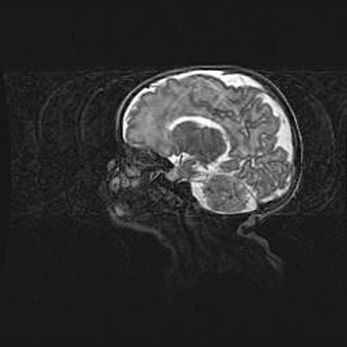

Мальформация Денди-Уокера. Киста задней черепной ямки.

Агенезия мозолистого тела.

Возраст: 2,5 месяца

Вес: 2420 г

Пол: женский

Окружность головы: 37 см

Срок гестации: 32 недели

Мальформация Денди—Уокера — редкий вид патологии ЦНС, представляющий собой врожденный порок развития каудального отдела ствола и червя мозжечка, ведущий к неполному раскрытию срединной (Мажанди) и латеральных (Лушка) апертур IV желудочка мозга. Для этогно синдрома характерна триада симптомов: гипотрофия червя мозжечка и/или полушарий мозжечка, кисты задней черепной ямки, гидроцефалия различной степени. В 70% случаев порок сочетается и с другими аномалиями головного мозга, в частности с агенезией мозолистого тела.